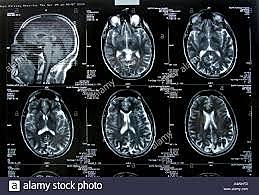

• Tomografía Axial  Computarizada

Tomografía Axial Computarizada

Godfrey Hounsdfield creó la prueba diagnóstica que permite obtener imágenes radiográficas del interior del organismo.